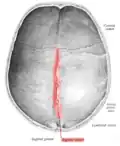

![]() Human adult skull from above | |

Animation. Sagittal suture shown in red. -

Sagittal suture seen from inside.